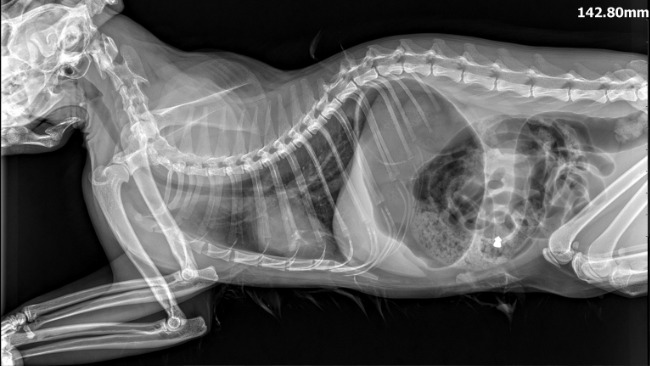

Na szczęście weterynarz zadzwonił do nas z pytaniem, czy możemy uratować Karmela i zaopiekować się nim. Pojechałyśmy po niego od razu. Rude cudo nie bardzo wiedziało, co się z nim dzieje. Szybko odbił w chorobie i zadomowił się u nas. I wszystko było dobrze, dopóki kilka dni temu nie zaczął koszmarnie źle oddychać, jakby nie mógł złapać haustu powietrza. Pojechałyśmy z nim na cito do kliniki. Od razu zrobiono mu RTG i USG. Weterynarz zmartwiło przede wszystkim zmniejszenie powietrzności dobrzusznych partii płuc. Poza tym na zdjęciu okazało się, że ma śrut w brzuchu.

Jego pobyt kosztował 1700 zł. Ten kot naprawdę wiele przeszedł, strzelano do niego, porzucono go, cudem przeżył pierwsze zapalenie otrzewnej i zapalenie płuc. Kochał dzieci, z którymi był od małego. Po jego oddaniu były właściciel zadzwonił do nas RAZ. Chciał wiedzieć, czy wszystko dobrze i czy dziewczynki będą mogły od czasu do czasu zadzwonić i zapytać o niego. Karmel jest u nas od końca stycznia. Więcej telefonów nie było. Karmel doskonale odnalazł się w nowym otoczeniu, ale prawda jest taka, że gdyby nie my, zostałby uśpiony. Nie zasłużył sobie na to!!!